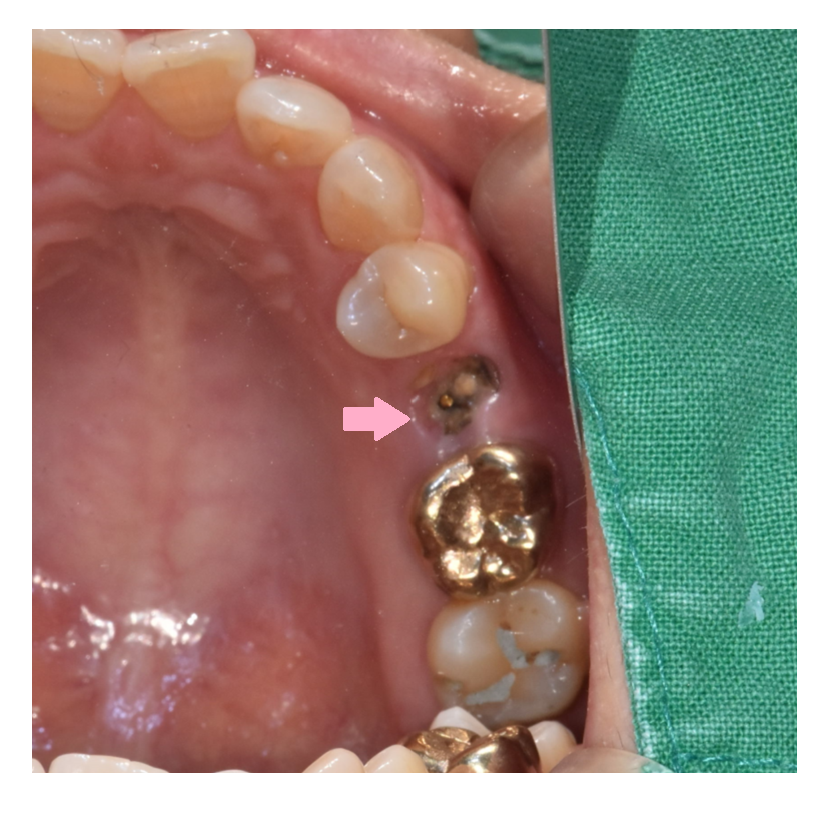

사진을 보시면 아시겠지만 뿌리만 남은 경우입니다.

거의 잇몸에 박혀있죠.